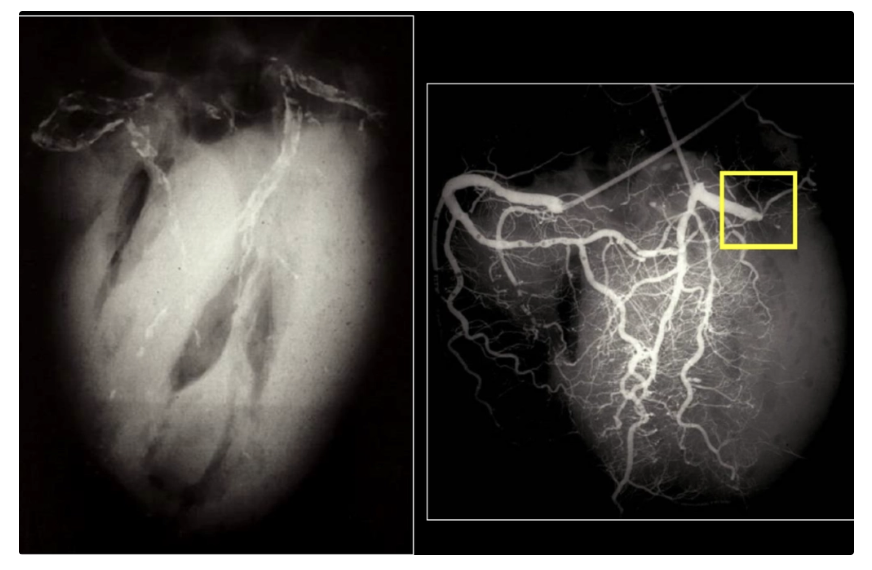

dark red recent coronary thrombosis